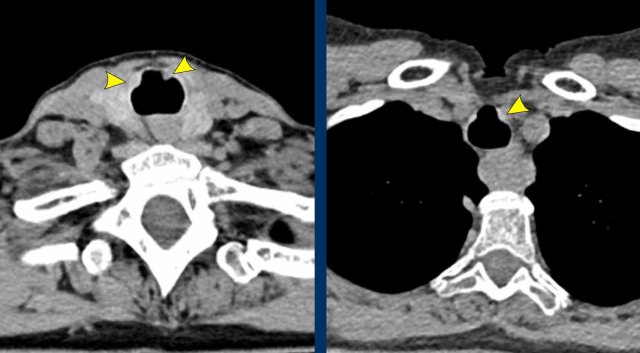

Image

Tracheobronchial

papillomatosis with lung involvement in a 54 y.o male, showing two papillomas

in the trachea.

Continue with the lung window...

The image shows multiple cystic lesions in both lungs (arrowheads).

In rare cases extension into the lung parenchyma can occur, showing cystic nodules most often in the dependent apical segments of the lower lobes. There is a small risk of malignant transformation from squamous cell papilloma into squamous cell carcinoma.